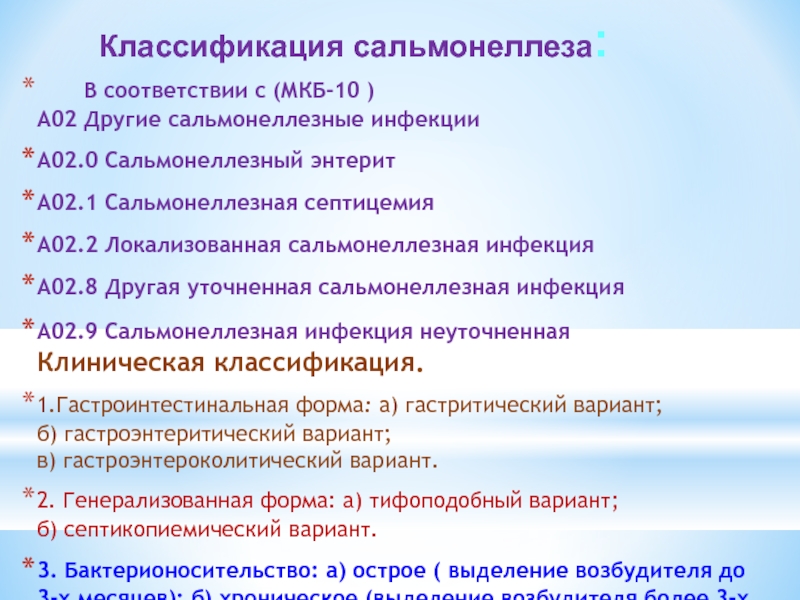

Острая внебольничная пневмония по МКБ-10: признаки и примеры